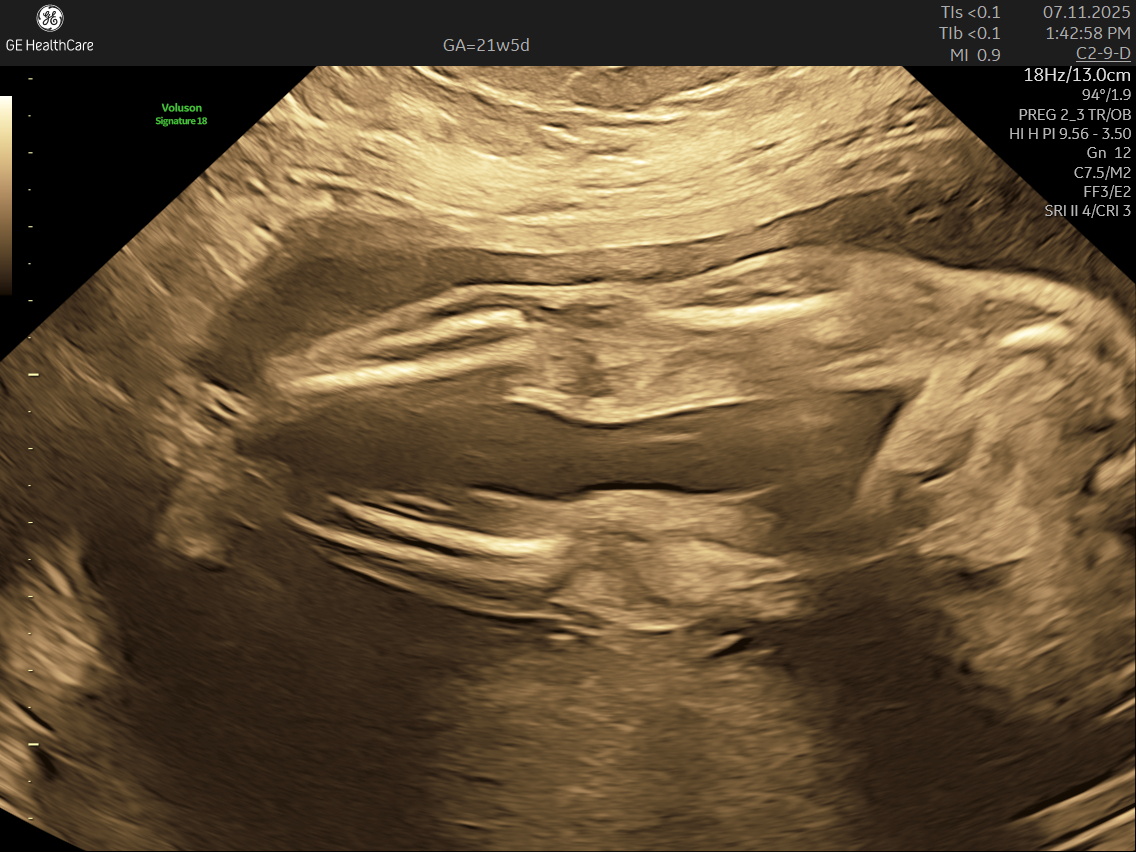

IMAGE GALLERY